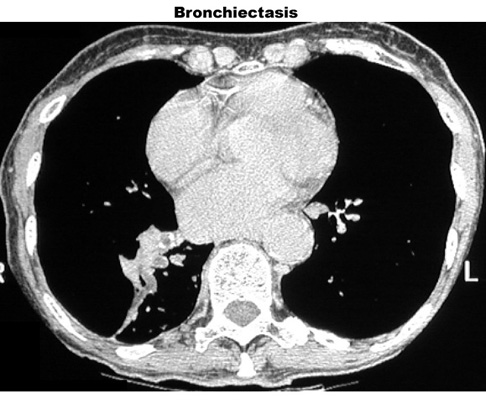

Bronchiectasis

Dilated bronchi with peribronchial fibrosis, visualized in various cuts of CT as cystic spaces, tubular shadows and branching densities.